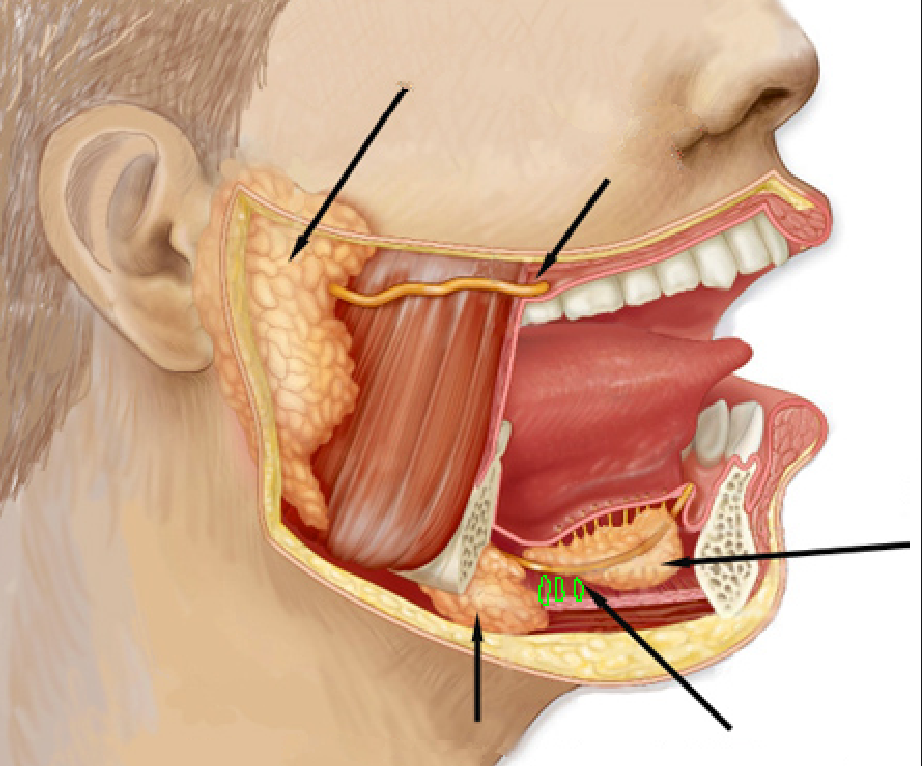

Submandibular gland

Submandibular ducts

Sublingual gland

Sublingual ducts

Openings of submandibular ducts